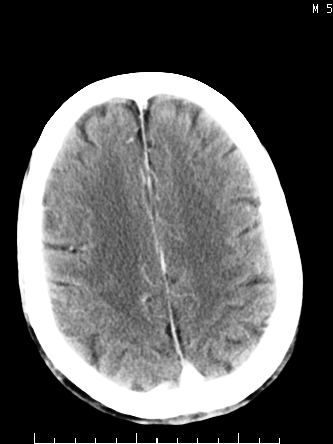

m/50,头昏头痛1月,近3天感觉左半肢体活动不利,自述半年前呈患肺tb,腰穿脑脊液未见特殊改变。现做头颅ct请大家会诊。

ct值?是囊变?梗塞软化灶形成

考虑颅内感染性病变:结核可能性大。

结核性脑膜炎,结核瘤,梗塞灶三症并存,提示颅内结核感染可能性大。

感染性病变;脑干脓肿(脓肿壁形成期),基底节及内囊(脑炎期)。顺便问一句,该病人是不是抵抗力很差,有没有糖尿病。

右侧基底节区缺血性脑梗塞.脑干区考虑结核.

可考虑结核,患者水肿范围大,囊性病灶边缘密度较高,不考虑胶质母细胞瘤